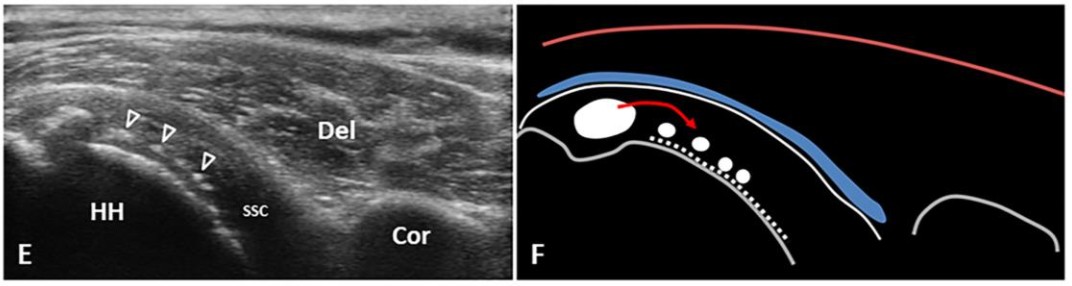

🖼 Hình SA-3 — Pha Resorptive: SSP sub-bursal migration (C,D) & SSC articular-side migration (E,F)

Mũi tên rỗng = mảnh vôi mềm sub-bursal (C,D). Đầu mũi tên rỗng = vôi articular-side hướng về HH (E,F). Mũi tên đỏ = hướng di động.

SA Resorptive phase migration

🖼 Hình SA-5 — Pha Post-Calcific: SSC articular-side migration → nguy cơ frozen shoulder (Hình 2E,F)

Long-axis SSC: các chấm vôi nhỏ (đầu mũi tên) hướng về mặt xương cánh tay (HH). Đây là kiểu di động có thể dẫn đến post-calcific frozen shoulder.

SA Post-calcific frozen shoulder